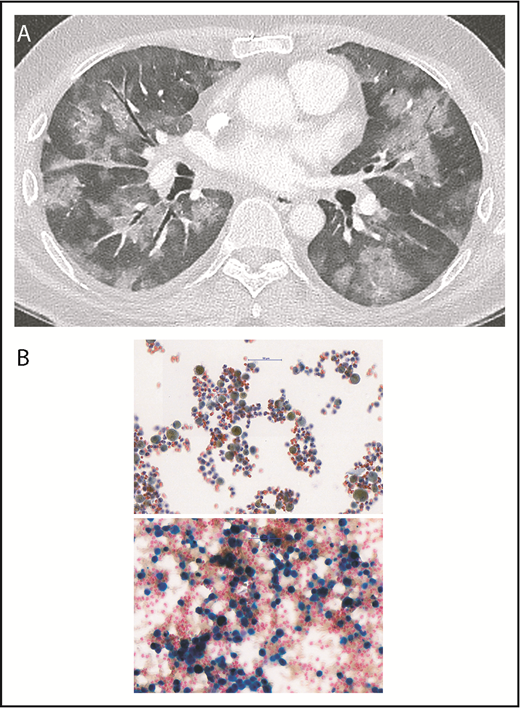

A contrast-enhanced thoracic-computer tomography showed bilateral diffuse ground-glass lesions, suggestive of alveolar hemorrhages (Figure 1A), without signs of pulmonary embolism or signs of active bronchial artery bleeding. A bronchoscopy confirmed the presence of blood within both lungs. Microbiologic tests and cultures for bacteria, fungi, viruses, and mycobacteria, as well as search for neoplastic cells from bronchoalveolar lavage, were negative. Cytological examination showed numerous macrophages intensely stained by Prussian blue, denoting iron, reflecting severe intra-alveolar hemorrhage (Figure 1B-C). Lupus anticoagulant was positive, and anticardiolipin and anti-β2-glycoprotein 1 immunoglobulin G antibody titers were very high (Figure 2). Notably, the rest of the immune-serological work-up showed that antinuclear antibodies were only transiently positive (1:320). However, anti-centromere proteins, anti-double stranded DNA, anti-nucleosomes, anti-histones, anti-RPN, anti-PCNA, anti-ribosomes, anti-SS-A and SS-B, anti-Scl-70, anti-RNA polymerase III, anti-Jo-1, anti-Mi-2, anti-Ku, anti-PM-Scl 100, anti-PR3-ANCA, anti-MPO-ANCA, and anti-glomerular basement membrane (Goodpasture) antibodies were negative. These results confirmed the diagnosis of primary APS. IV methylprednisolone boluses followed by oral prednisone were administered (Figure 2). To rapidly reduce APL titers, immunoadsorption on protein A column was conducted (5 courses during a 10-day period, each processing the patient’s plasma volume at least twice). Dyspnea improved promptly after the first immunoadsorption course. To enhance immunosuppression, rituximab was administered (Figure 2). On the eleventh day, the patient was discharged on enoxaparin (80 mg twice daily) and oral prednisone (80 mg/d). Prednisone was slowly tapered and withdrawn after 3 months.

Diffuse alveolar hemorrhage. (A) The contrast-enhanced thoracic-computer tomography shows widespread patchy ground glass opacification and, in part, a faint “crazy paving” pattern. The contrast between the ground glass areas caused by diffuse alveolar hemorrhage and the air containing bronchi render the bronchi more prominent (dark bronchus sign). There were no signs of pulmonary embolism nor signs of active bronchial artery bleeding. (B) Images of cytological bronchoalveolar lavage specimens. (Upper) Routine Papanicolaou staining shows macrophages (50%-60%) and a significant number of neutrophils, as well as lymphocytes. Almost all macrophages contain a brown-yellow pigment in the cytoplasm. (Lower) Prussian blue staining shows an area with more prominent macrophages, of which most stain intensely blue, denoting iron, reflecting severe intra-alveolar hemorrhage (∼95% of the total macrophage population were hemosiderin-laden macrophages, Golde score 250). Magnification, 40×.